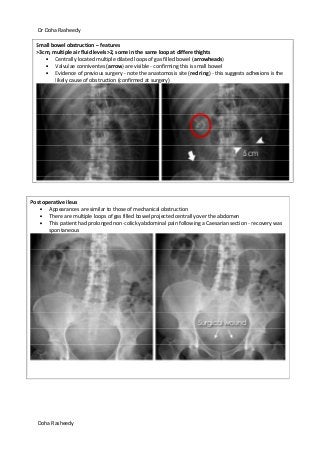

Small bowel obstruction – features

>3cm, multiple air fluid levels>2, some in the same loop at differe thights

Centrally located multiple dilated loops of gas filled bowel (arrowheads)

Valvulae conniventes (arrow) are visible - confirming this is small bowel

Evidence of previous surgery - note the anastomosis site (red ring) - this suggests adhesions is the

likely cause of obstruction (confirmed at surgery)

Post operative ileus

Appearances are similar to those of mechanical obstruction

There are multiple loops of gas filled bowel projected centrally over the abdomen

This patient had prolonged non-colicky abdominal pain following a Caesarian section - recovery was

spontaneous